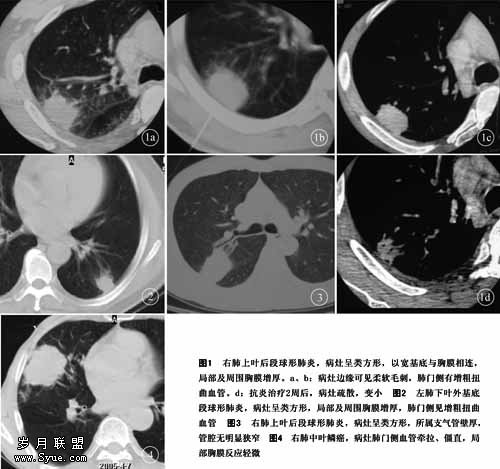

2.1 病灶部位 右肺21例,左肺11例。两肺下叶后基底段、外侧段及背段23例(72%),上叶8例,右肺中叶2例。29例位于胸膜下并与之相连,其中26例与胸膜广基相连(图1a~c),仅3例位于肺叶近中心,与胸膜距离较大。

2.2 形态大小 CT上28例病灶不同层面呈类楔形高密度影,尖端朝向肺门,其中21例可见1~4层以胸膜为基底,两侧缘垂直胸膜呈类方形(图1a~c、图2);7例呈山丘状类高张三角形。4例呈不规则类圆形。病变大小2~7 cm,平均3.8 cm。

2.3 病灶边缘 大部分侧缘清楚,但不锐利。于肺窗图像上25例可见边缘较均匀分布的柔软短毛刺(图1a、图1b),纵隔窗毛刺消失,呈边缘光滑、多浅分叶(波浪状),仅7例侧缘相对光整。

2.5 胸膜改变 与胸膜相连的29例中26例有局部及周围胸膜增厚(图1a~c、图2),其中17例与胸壁间有低密度带(脂肪密度),3例非与胸膜相贴的病例中2例见胸膜侧索条影。未见明显胸膜腔积液征象。

2.6 肺门侧表现 19例病变肺门侧有多条增粗的血管影大多扭曲明显,无明显僵直和牵拉(图1a、图1b、图2 )。8例病变所属段叶支气管壁较均匀广泛增厚,管腔无明显狭窄(图3)。

2.8 抗炎后8天~3周 25例病灶变疏散,失去原有形态(图1d),7例自病灶周围呈融冰状缩小。13例经抗炎治疗2周病灶基本吸收,16例治疗3~4周基本吸收,另3例5周~5个月基本吸收。32例中21例完全吸收,余11例遗留局部少许索条影,同时增厚的胸膜和肺门侧增粗扭曲的血管恢复正常。所有病例首诊全部CT检查和25例同时(3天内)摄X线胸部平片。7例用X线平片随访,19例CT和X线平片共同间隔或同时动态观察病灶变化,6例只用CT观察。

3.3 影像学特征 只有明确肺部病变基本形态,才能划出疑诊范围。X线胸部平片能显示大部分病变,但对病变基本细节和周围结构(伴随改变)显示不如CT。笔者认为球形肺炎的CT表现具有一定的特征,有助于诊断和鉴别诊断。(1)病变形态:名曰球形肺炎,而少见呈圆球形,多为以胸膜为基底的方形、楔形或三角锥形。而周围型肺癌多为类圆形。以胸膜为基底,两侧缘垂直于胸膜呈刀切样边缘或呈类方形征(图1~3),于1996年和1999年分别明确提出[1,2]是球形肺炎的特征。临床实践中,1995年以后的13例有此征象者无一误诊,相关文献亦明确证实[3~5]。尚未见肺癌和结核球等病变有此表现。(2)球形肺炎病灶边缘大多模糊,可伴有较多均匀分布的长且柔软的毛刺(图1a、图1b、图2 ),周围型肺癌常因肿瘤浸润性生长,瘤间质反应形成不均匀分布的细短毛刺。(3)胸膜增厚:以胸膜为基底的绝大多数病灶局部和周围胸膜炎性反应性均匀增厚,无明显结节,且与非增厚胸膜界限清楚(图1c、图1d);无明显胸膜腔积液亦是球形肺炎的特征之一。本组病例该种表现率较高,为89.7%(26/29)。与肺癌和肺结核形成的胸膜凹陷征不同,有胸膜的牵拉凹陷及液体积聚[6,7]。至于周围型肺癌的胸膜直接侵犯,邻近胸膜较少受累。Ratto应用肿瘤—胸膜接触面长度和肿瘤直径之比<0.9为标准,其敏感性和特异性各为83%和80%[8]。球形肺炎所致胸膜增厚范围大于病灶直径,抗炎治疗后胸膜增厚消失,很少遗留有胸膜增厚。(4)球形肺炎病灶肺门侧多条增粗扭曲血管,但无僵直及牵拉(图1a、图1b、图2 )。有别于肺癌造成的血管集中征,肺血管被牵拉僵直,向肿瘤移位(图4 )。(5)球形肺炎病变所属段及亚段支气管均匀性增厚,而无明显狭窄,同级支气管在CT上显示率明显强于非病变区支气管(图5 )。纤维支气管镜检查可见到所属支气管黏膜充血、水肿。周围型肺癌若累及支气管,则表现为受累支气管的不规则狭窄。纤维支气管镜可见到受累支气管新生物[3]。(6)球形肺炎为急性渗出性炎症,少有纵隔和肺门淋巴结肿大。周围型肺癌往往会有转移性淋巴结肿大。(7)病灶非胸膜侧浅淡小片状高密度影是支持肺炎性病变的征象。(8)球形肺炎病灶密度,本组病例有18例(18/32)表现病灶中心密度高,周围密度较低的晕圈样,但在肿瘤、结核等病变亦可见到,不能过分强调其鉴别诊断价值,如同病灶内可见到充气支气管一样,也是周围型肺癌的常见征象。(9)球形肺炎影像学大体表现类似于周围型肺癌,但抗炎治疗一旦出现病灶疏散的表现或明显缩小,可作为排除肺癌而支持肺炎诊断的征象。但是,要注意有不少病例有延迟吸收现象。